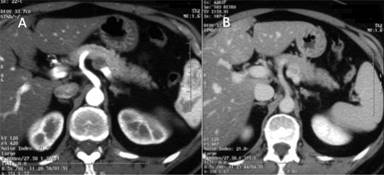

A fifty eight year old woman was admitted to our Department for dull epigastric and left hypocondrium pain, with no other associated symptoms. She had no history of diabetes, previous cancer, pancreatic disease and alcohol or tobacco addiction. Her physical examination and blood tests were normal. An abdominal ultrasound scan was performed and found to be normal except for a 2-cm hypoechoic lesion identified along the posterior margin of the pancreatic body. A chest-abdomen CT scan was then performed, confirming a 15 mm mainly hypodense lesion along the posterior margin of the pancreatic body (Figure 1). The lesion was in close contact with the splenic vessels, which were patent with no sign of thrombosis. No lymphadenopathy or distant metastatic deposit was detected. Alpha-fetoprotein, carcinoembryonic antigen, carbohydrate antigen 19.9 and chromogranin A were normal. The differential diagnosis included metastasis, pancreatic adenocarcinoma, endocrine tumor, extra-intestinal gastro-intestinal stromal tumor, Schwannoma, inflammatory myofibroblastic tumor and fibrous solitary tumor of the pancreas.